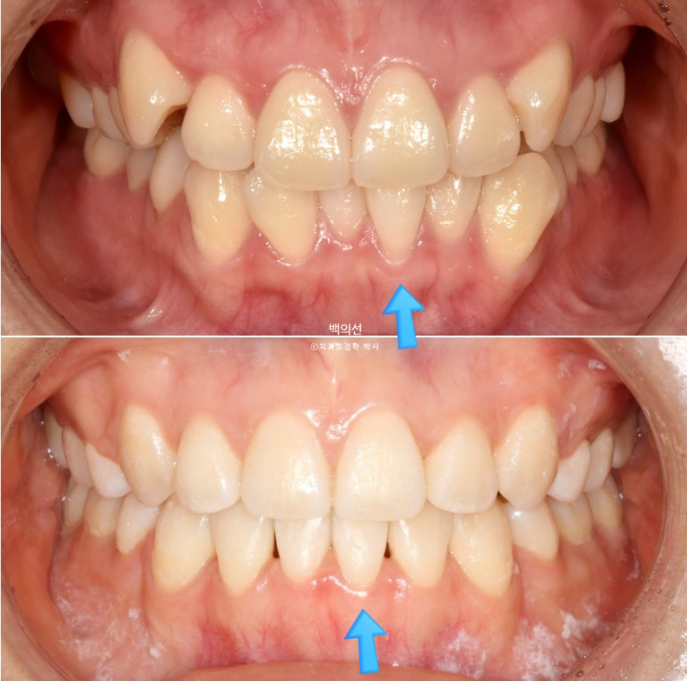

이제 전후 비교 보겠습니다

치아끼리 심하게 겹쳐져 있던 부위에 블랙트라이앵글은 아쉽지만 잇몸이 내려가 있었던 다수의 치아들에서 잇몸이 다시 차오른 것을 볼 수 있습니다.

통상 한 번 내려간 잇몸은 다시 차오르지 않는다고 알려져 있지만

잇몸이 내려간 원인이 만약 치아가 자리가 없어 밀려나 있었기 때문이라면, 발치교정을 통해 밀려난 위치에서 안정적인 위치로 움직이는 과정에서 잇몸이 다시 차오를 수 있습니다.

물론 20대 초반의 젊은 성인에서 가능한 이야기지만요.